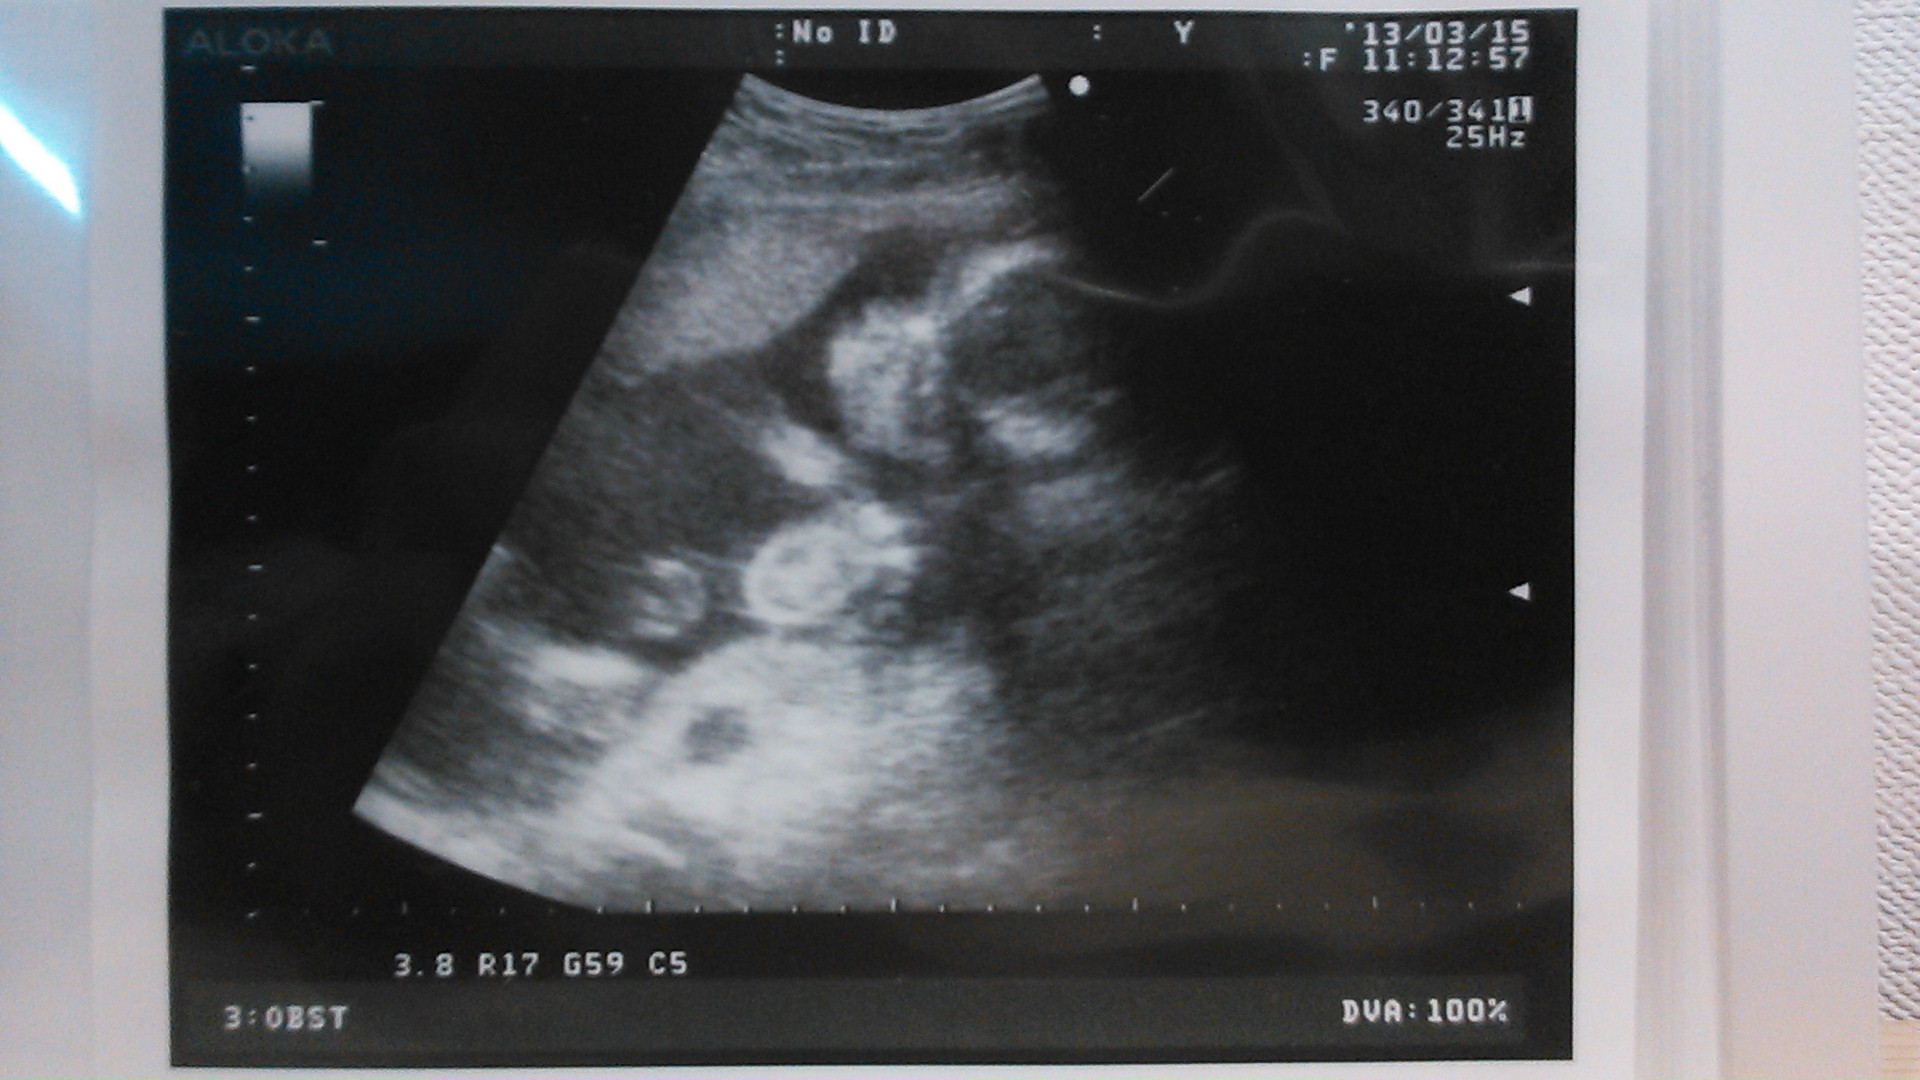

echo